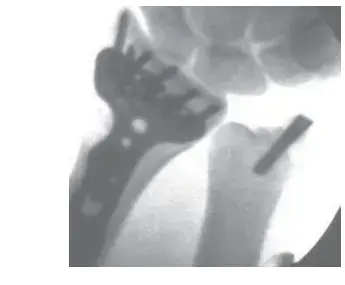

أ. التثبيت النخاعي (Intramedullary Nailing - IMN)

يعتبر التثبيت النخاعي أحد التقنيات الرائدة والفعالة لعلاج كسور قصبة الساق. يتميز بإدخال مسمار معدني مجوف (Nail) داخل القناة النخاعية لقصبة الساق، وهو ما يوفر تثبيتاً قوياً ومحورياً.

- يتم إدخال المسمار النخاعي من أعلى (عبر الركبة) أو من أسفل (عبر الكاحل) وتثبيته بمسامير عرضية (Locking Screws) في كلا الطرفين العلوي والسفلي، مما يمنع الدوران أو القص.

- يساعد هذا النوع من التثبيت على مشاركة الحمل (Load Sharing) بين المسمار والعظم، مما يقلل من إجهاد المعدن ويساعد على تحفيز التئام العظم.

* يتم إدخال المسمار النخاعي، الذي تم اختياره مسبقاً بناءً على قياسات التخطيط، بعناية فائقة فوق الدليل السلكي. يتم دفعه ببطء وثبات حتى يعبر خط الكسر ويصل إلى وضعية الاستقرار المطلوبة في الجزء القاصي من قصبة الساق. يتم التحقق من وضع المسمار باستمرار باستخدام جهاز التصوير بالأشعة (Fluoroscopy) لضمان المحاذاة الصحيحة وتجنب أي اختراق للمفصل.

6. قفل المسمار (Locking):

* بعد أن يستقر المسمار النخاعي في مكانه الصحيح، يتم تثبيته بواسطة مسامير قفل عرضية (Locking Screws) في كلا الطرفين العلوي والسفلي. تمنع هذه المسامير المسمار من الدوران أو الانزلاق داخل العظم، وتوفر استقراراً كاملاً للكسر.

مسامير القفل القاصية (Distal Locking Screws):

هذه هي الأكثر أهمية في الكسور الممتدة إلى الكاحل. يتم إدخالها بدقة متناهية بالقرب من مفصل الكاحل لتثبيت الجزء المفصلي الذي تم إعادة بنائه. غالباً ما تستخدم تقنيات التوجيه بالكمبيوتر أو أدوات توجيه خاصة (Jigs) لضمان دقة إدخال هذه المسامير.